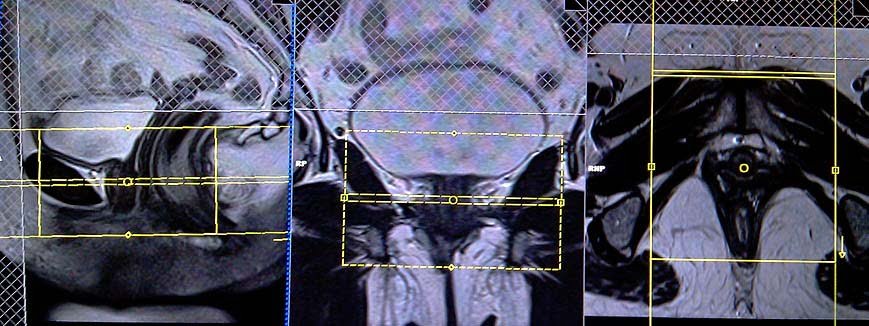

T2 tse fat sat (or stir) axial OBLIQUE 3mm small fov

Plan the axial slices on the sagittal plane; angle the positioning block perpendicular to the urethra. Check the positioning block in the other two planes. An appropriate angle must be given in the coronal plane (perpendicular to the urethra). The slices must be sufficient to cover the whole urethra from the mid-urinary bladder down to 1 inch below the opening of the urethra. Use a smaller FOV around 130-150mm. Adding saturation bands on top and in front of the axial block will reduce artifacts from arterial pulsation, peristalsis, and breathing.

Parameters

TR 4000-5000 | TE 110 | FLIP 160 | NEX 4 | SLICE 3MM | MATRIX 224X208 | PHASE A>P | GAP 10% | FATSAT SPAIR |

T2 tse axial oblique 3mm small fov

TR 3000-4000 | TE 110 | FLIP 160 | NEX 4 | SLICE 3MM | MATRIX 256X224 | PHASE A>P | GAP 10% | FATSAT OFF |